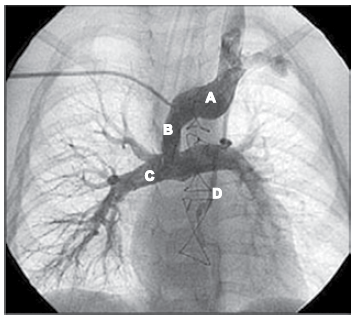

Observe a figura.

Essa imagem diz respeito ao seguinte procedimento cirúrgico: